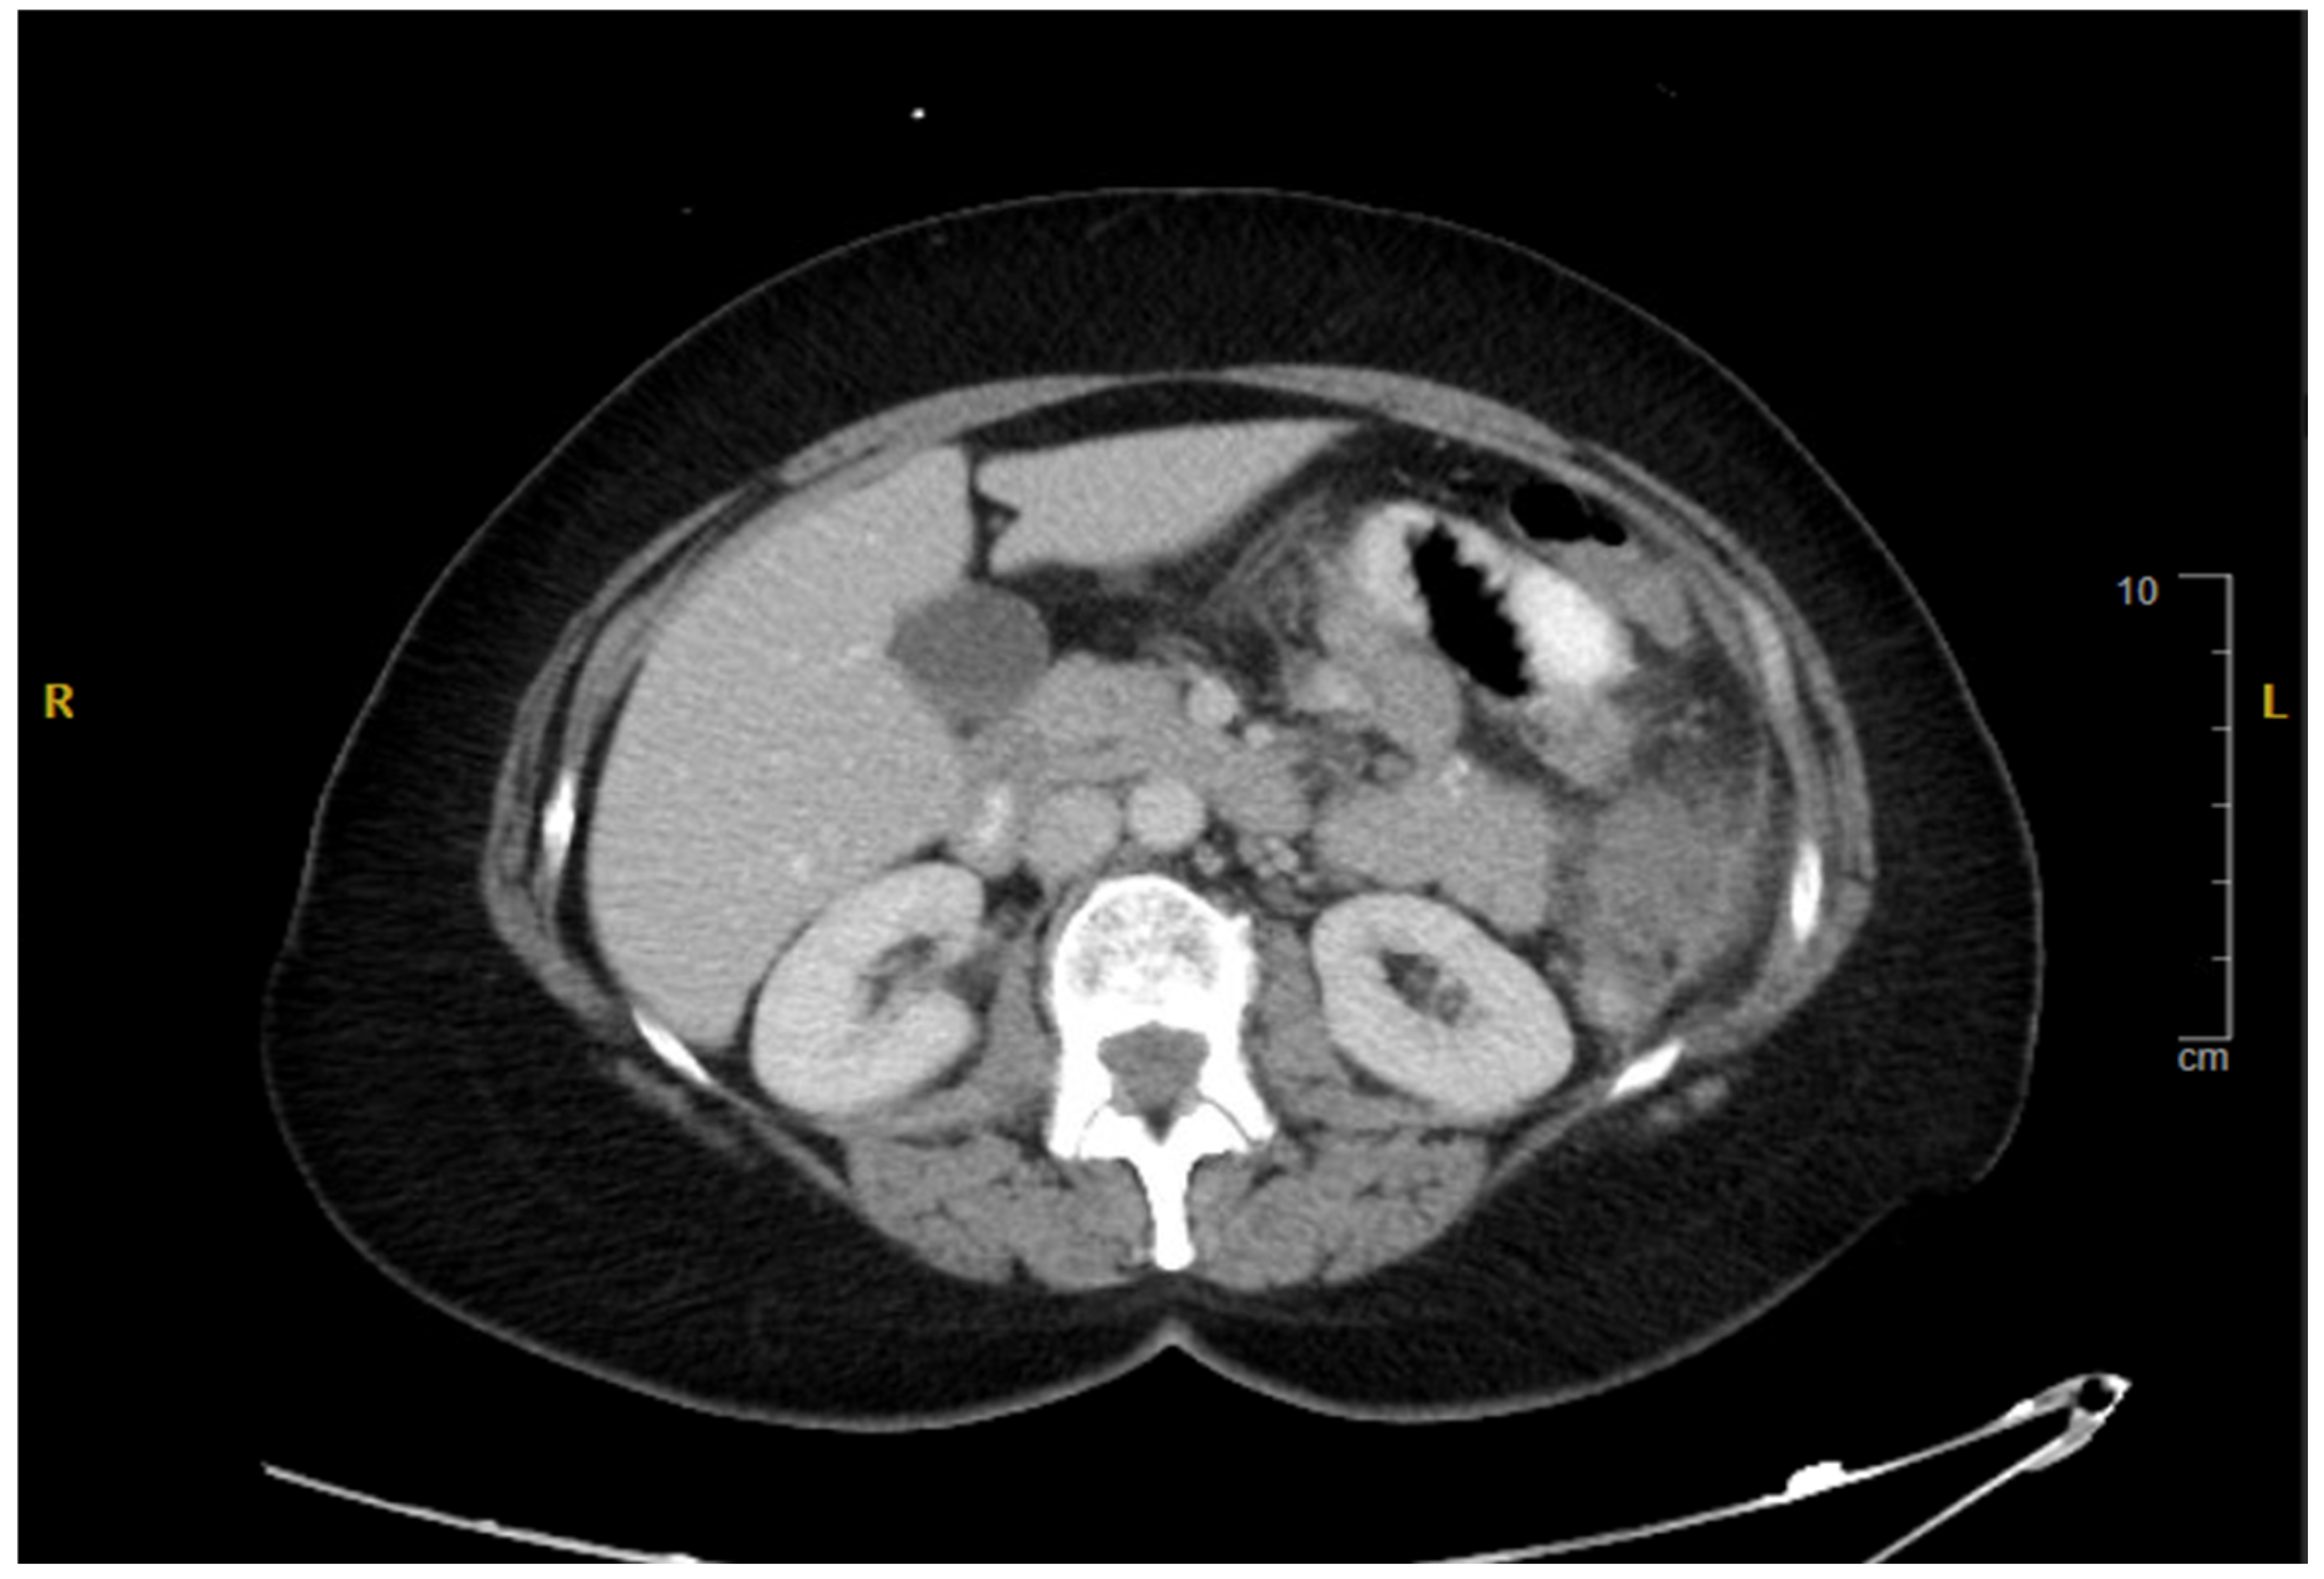

2. Case Presentation